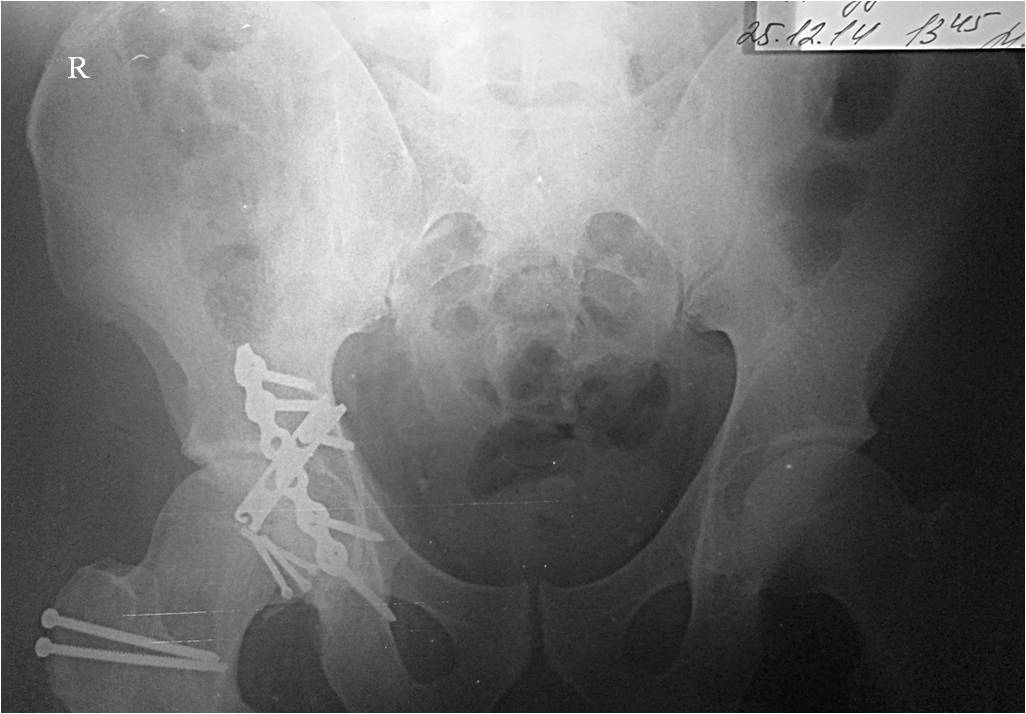

Через 12 дней выполнен остеосинтез головки 3-мя самокомпрессирующими

винтами Герберта. Доступ Kocher-Langenbeck с флип-остеотомией большого

вертела и задним хирургическим вывихом головки бедра. Интерпонирующий

внутрисуставной фрагмент представлял собой лабрум с тонкой костной

пластинкой от заднего края впадины. Фрагмент извлечен и фиксирован

техникой spring-plate.